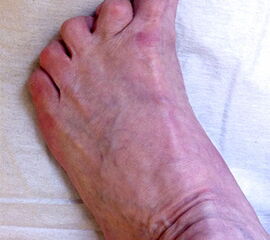

Klinisches Erscheinungsbild eines Hallux varus (eigenes Bildmaterial)

Abbildung 1